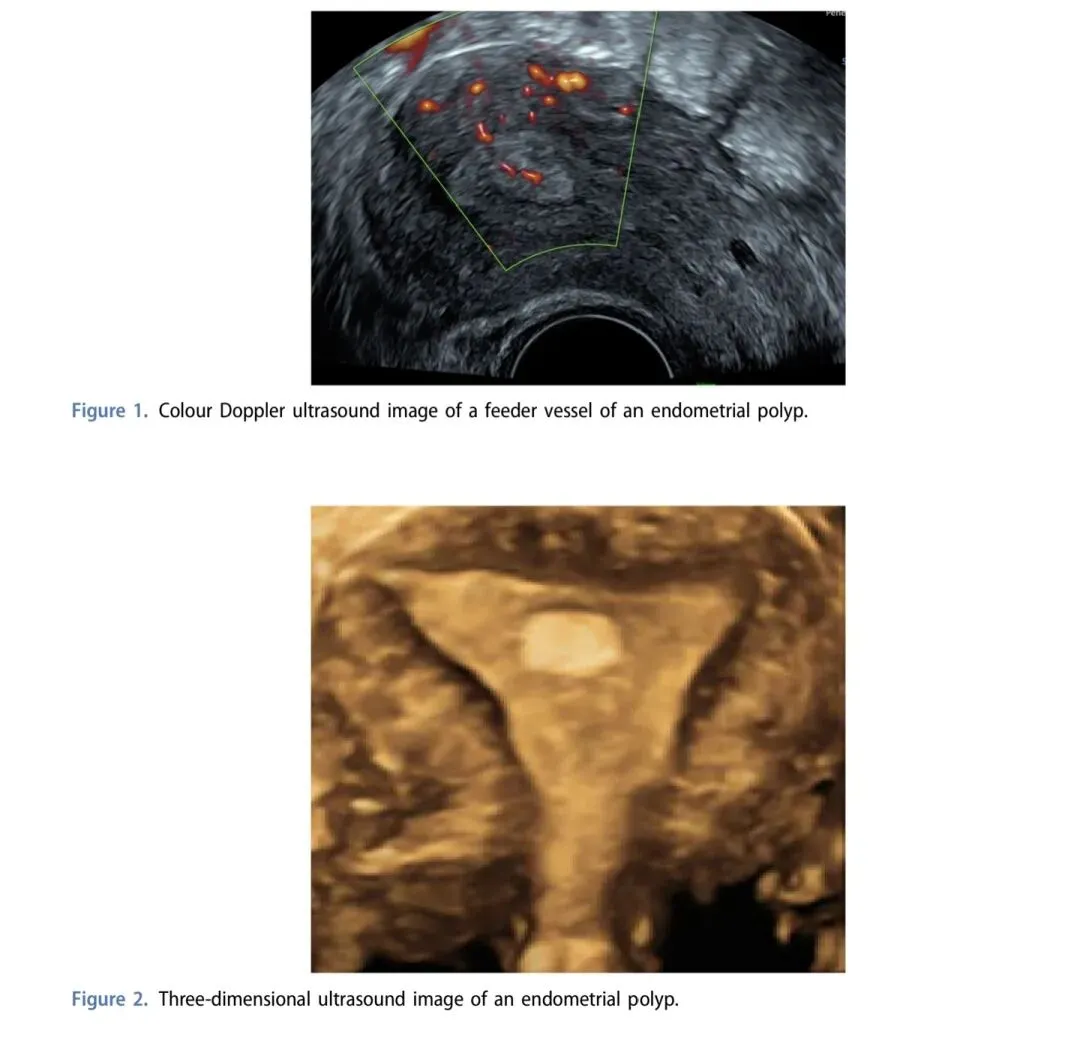

1. 彩色多普勒:识别息肉滋养血管(蒂动脉征),敏感度94%、特异度100%